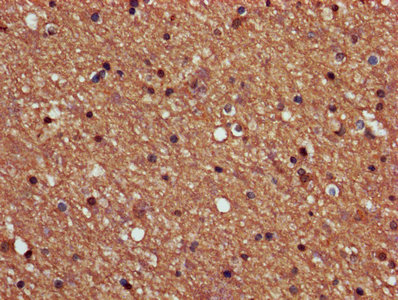

ApplicationELISA, IHC, IF; Recommended dilution: IHC:1:500-1:1000, IF:1:200-1:500